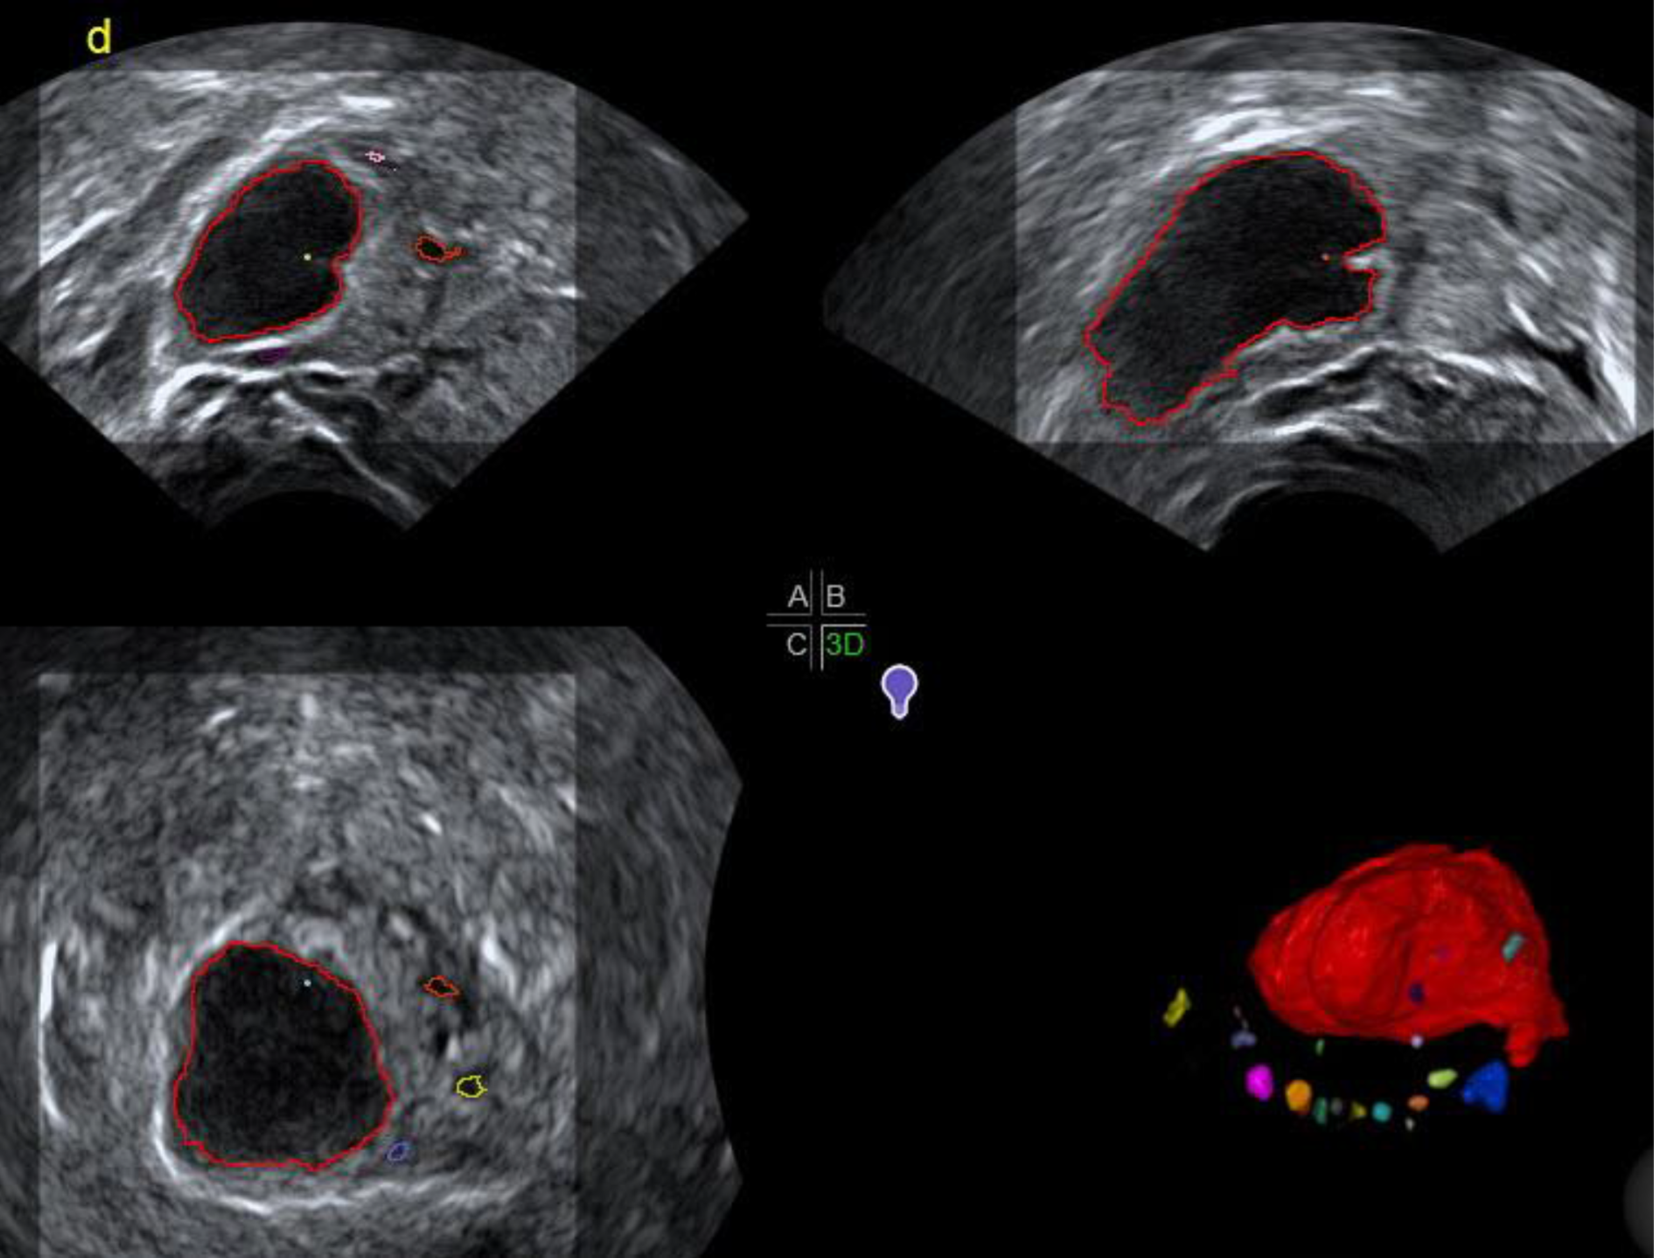

Der 3‑D-Ultraschall kann bei der Darstellung des Corpus luteum diagnostisch durchaus hilfreich sein: Die Tomographic-ultrasound-Methode ermöglicht es, in vorher gewählten Abständen bis zu 9 Schnitte des Ovars nebeneinander am Bildschirm darzustellen und sich ein Bild von dem CL innerhalb des Ovars zu machen (Abb. 5). Die Sono-AVC™-Methode hat ihren idealen Einsatz in der ersten Zyklushälfte. Bei einem deutlich flüssigkeitsgefüllten Corpus luteum kann dieses als irregulär umrandete Struktur dargestellt werden (Abb. 6). Die manuelle 3‑D-Darstellung des Corpus luteum mit dem integrierten Grafikprogramm kann nur offline nach der eigentlichen Untersuchung durchgeführt werden. Der diagnostische Mehrwert ist begrenzt (Abb. 7; [2]).

Abb. 6

Corpus luteum (rot) mit Sono-AVC. Im Gegensatz zu einem kreisrunden präovulatorischen Follikel ist das Corpus luteum längsoval mit lokalen Eindellungen

Abb. 7

Die manuelle 3‑D-Darstellung des Corpus luteum mit dem integrierten Grafikprogramm kann nur offline nach der eigentlichen Untersuchung durchgeführt werden. Der diagnostische Mehrwert ist überschaubar